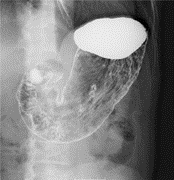

乳房X線撮影(マンモグラフィ)

乳房専用のX線撮影で、乳房内の微細な石灰化やしこりなど、早期乳がんの発見に非常に有効な画像検査です。 検査では触診だけではわかりにくい病変を画像化するために、乳房を圧迫して薄く均等な厚みにして検査します。

この際、圧迫による痛みを感じることがありますが、痛みが強い場合は、我慢せずに担当技師に伝えてください。当院では女性の認定技師が撮影を行っております。